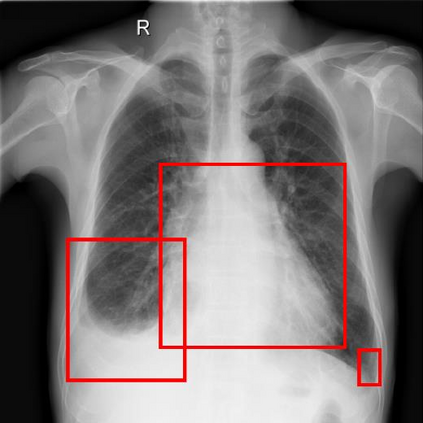

Chest X-ray (CXR) is the most typical diagnostic X-ray examination for screening various thoracic diseases. Automatically localizing lesions from CXR is promising for alleviating radiologists' reading burden. However, CXR datasets are often with massive image-level annotations and scarce lesion-level annotations, and more often, without annotations. Thus far, unifying different supervision granularities to develop thoracic disease detection algorithms has not been comprehensively addressed. In this paper, we present OXnet, the first deep omni-supervised thoracic disease detection network to our best knowledge that uses as much available supervision as possible for CXR diagnosis. We first introduce supervised learning via a one-stage detection model. Then, we inject a global classification head to the detection model and propose dual attention alignment to guide the global gradient to the local detection branch, which enables learning lesion detection from image-level annotations. We also impose intra-class compactness and inter-class separability with global prototype alignment to further enhance the global information learning. Moreover, we leverage a soft focal loss to distill the soft pseudo-labels of unlabeled data generated by a teacher model. Extensive experiments on a large-scale chest X-ray dataset show the proposed OXnet outperforms competitive methods with significant margins. Further, we investigate omni-supervision under various annotation granularities and corroborate OXnet is a promising choice to mitigate the plight of annotation shortage for medical image diagnosis.